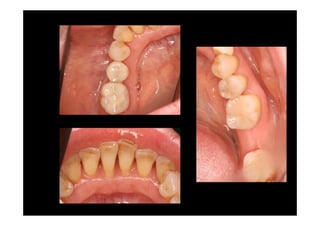

Surgery

Removing granulation tissue and

osteoplasty

3 months control

7 months control